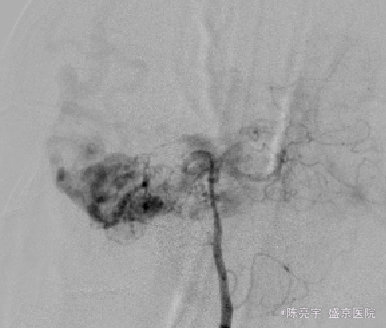

主诉:头痛加重3天 现病史:患者突发头痛,当时患者出现头部双侧太阳穴处胀痛,疼痛呈间断性,可忍受,伴有恶心呕吐感,完善相关检查,结果提示:动静脉畸形可能性大。现患者来我院进一步确诊治疗。患者现无意识障碍,无抽搐,无二便失禁,无恶心,呕吐。无视力视野障碍,二便饮食良好。

诊断:颅内血管畸形 治疗:全麻下血管畸形介入栓塞术